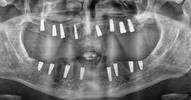

Implant Treatment

Periimplantitis

Peri-Implant Mucositis